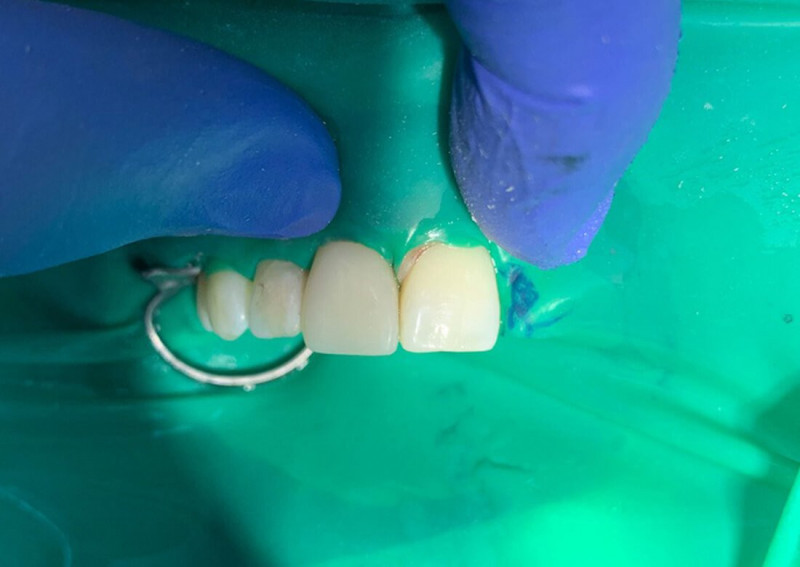

Установка виниров

Установка виниров E-max

Установка виниров E-max

Установка виниров E-max

Установка виниров E-max

Установка виниров E-max

Установка виниров

Установка виниров E-max